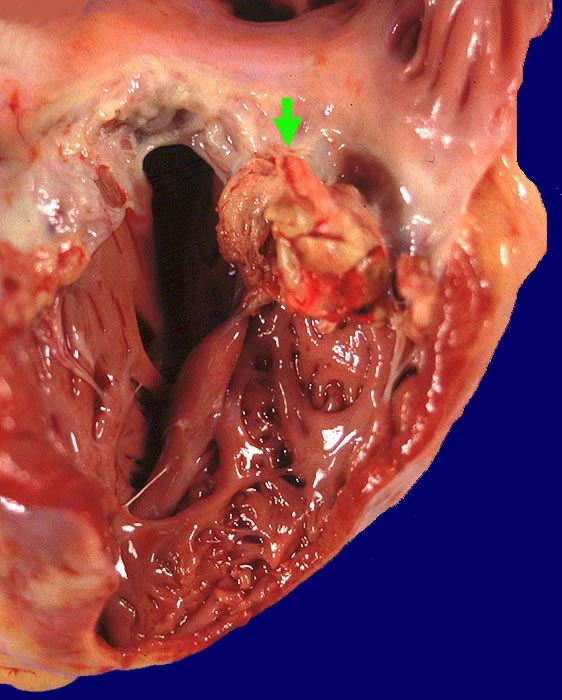

AP/ Infektiöse Endocarditis ulcero-polyposa

Infektiöse Endocarditis ulcero-polyposa

Makroskopisch sind entweder flache rötliche fibrinbelegte Ulzera (=ulcerosa (> 2935)) oder zusätzlich weiche gelbbraune bröcklige erbs- bis pflaumengrosse Polypen (=ulceropolyposa (> 2936) (> 8376)) oder ausschliesslich polypoide Fibrinbeläge (=marantica) auf einem Endokarddefekt oder einer partiell zerstörten Klappe erkennbar.

Histologisch findet sich bei ulzeropolypöser Endokarditis ein Fibrin-Thrombozytenthrombus, welcher von Bakterien durchsetzt ist (=Vegetation). Die Vegetation sitzt auf einem Klappendefekt an dessen Basis Granulationsgewebe einzusprossen beginnt, welches den Thrombus organisiert. Klappendefekte, Gefässeinsprossungen, verdickte Sehnenfäden (> 2848) oder Kommissurenverwachsungen (> 8389) der Taschenklappen weisen morphologisch auf eine abgeheilte Endokarditis hin.

• Längsschnitt durch Aorta, Aortenklappe und linkes Ventrikelmyokard.

• Oben im Bild die Aorta mit kleinem Fibroatherom.

• Abszedierende Entzündung der aortalen Adventitia ausgehend von septikopyämischen Streuherden.

• Ulzerierte Aortenklappe(ulcerosa).

• Dem ulzerierten Klappengerüst aufgelagerte polypöse Vegetation aus Fibrin und Granulozyten durchsetzt von blauen Kokkenbakterienkolonien (polyposa).

• Ausgedehnte frische Koagulationsnekrose (unsichtbare Zellkerne, Infiltrate neutrophiler Granulozyten) des linken Ventrikelmyokards unterhalb der Klappe.

• Mehrere septikopyämische Streuherde (blaue Bakterienhaufen in intramyokardialen Blutgefässen umgeben von Mikroabszessen).